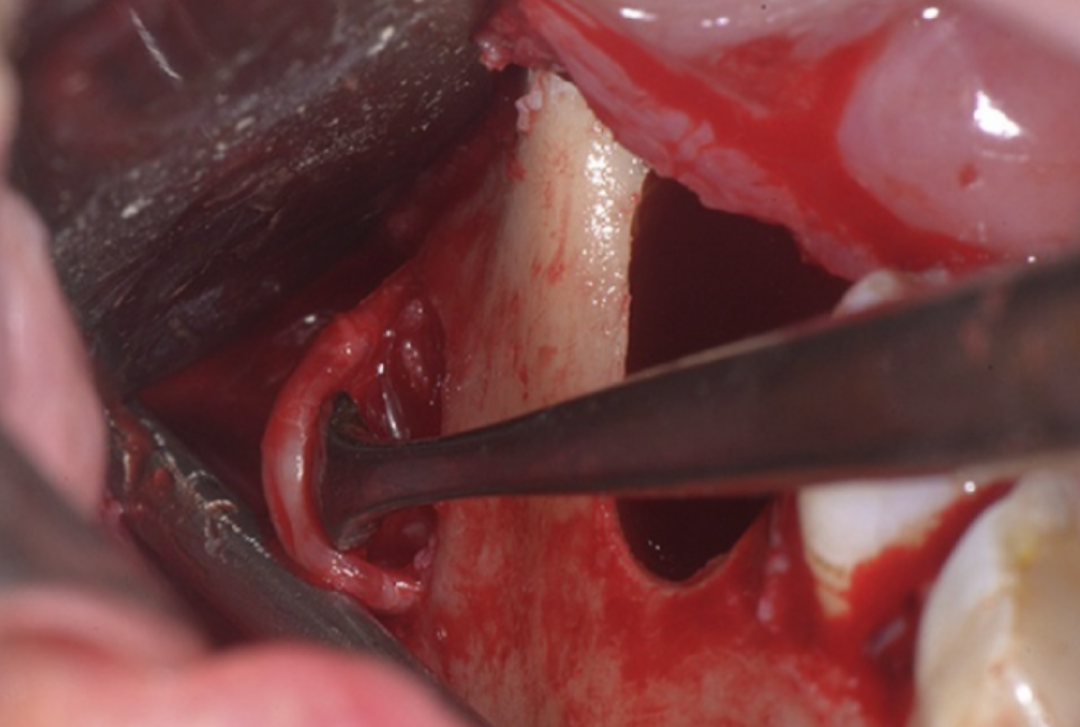

图4 分离后且非常清晰的下牙槽神经

下牙槽神经被提起后,骨板上的凹槽显露出来。进一步对CT图像进行检查,确认下颌神经从颊侧骨板穿出,并且在神经与囊肿之间存在正常骨质,下颌神经在一个开放的通道内自由移动。

这个放射学发现得到了临床验证:在摘除囊肿后,仍然存在坚实的骨质,左侧下颌神经的放射学检查显示其解剖结构正常。为了保护下颌神经,实施了牙冠切除术,并缝合了术区。术后3个月复查未发现下牙槽神经分布区域有感觉异常,复查的全景片显示骨愈合良好,剩余牙根位置稳定。组织病理学特征与牙源性囊肿一致,囊壁存在慢性炎症浸润,并被炎性鳞状上皮覆盖。